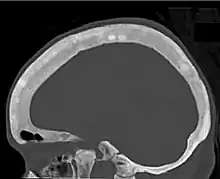

Ground glass density of the skull.[18]